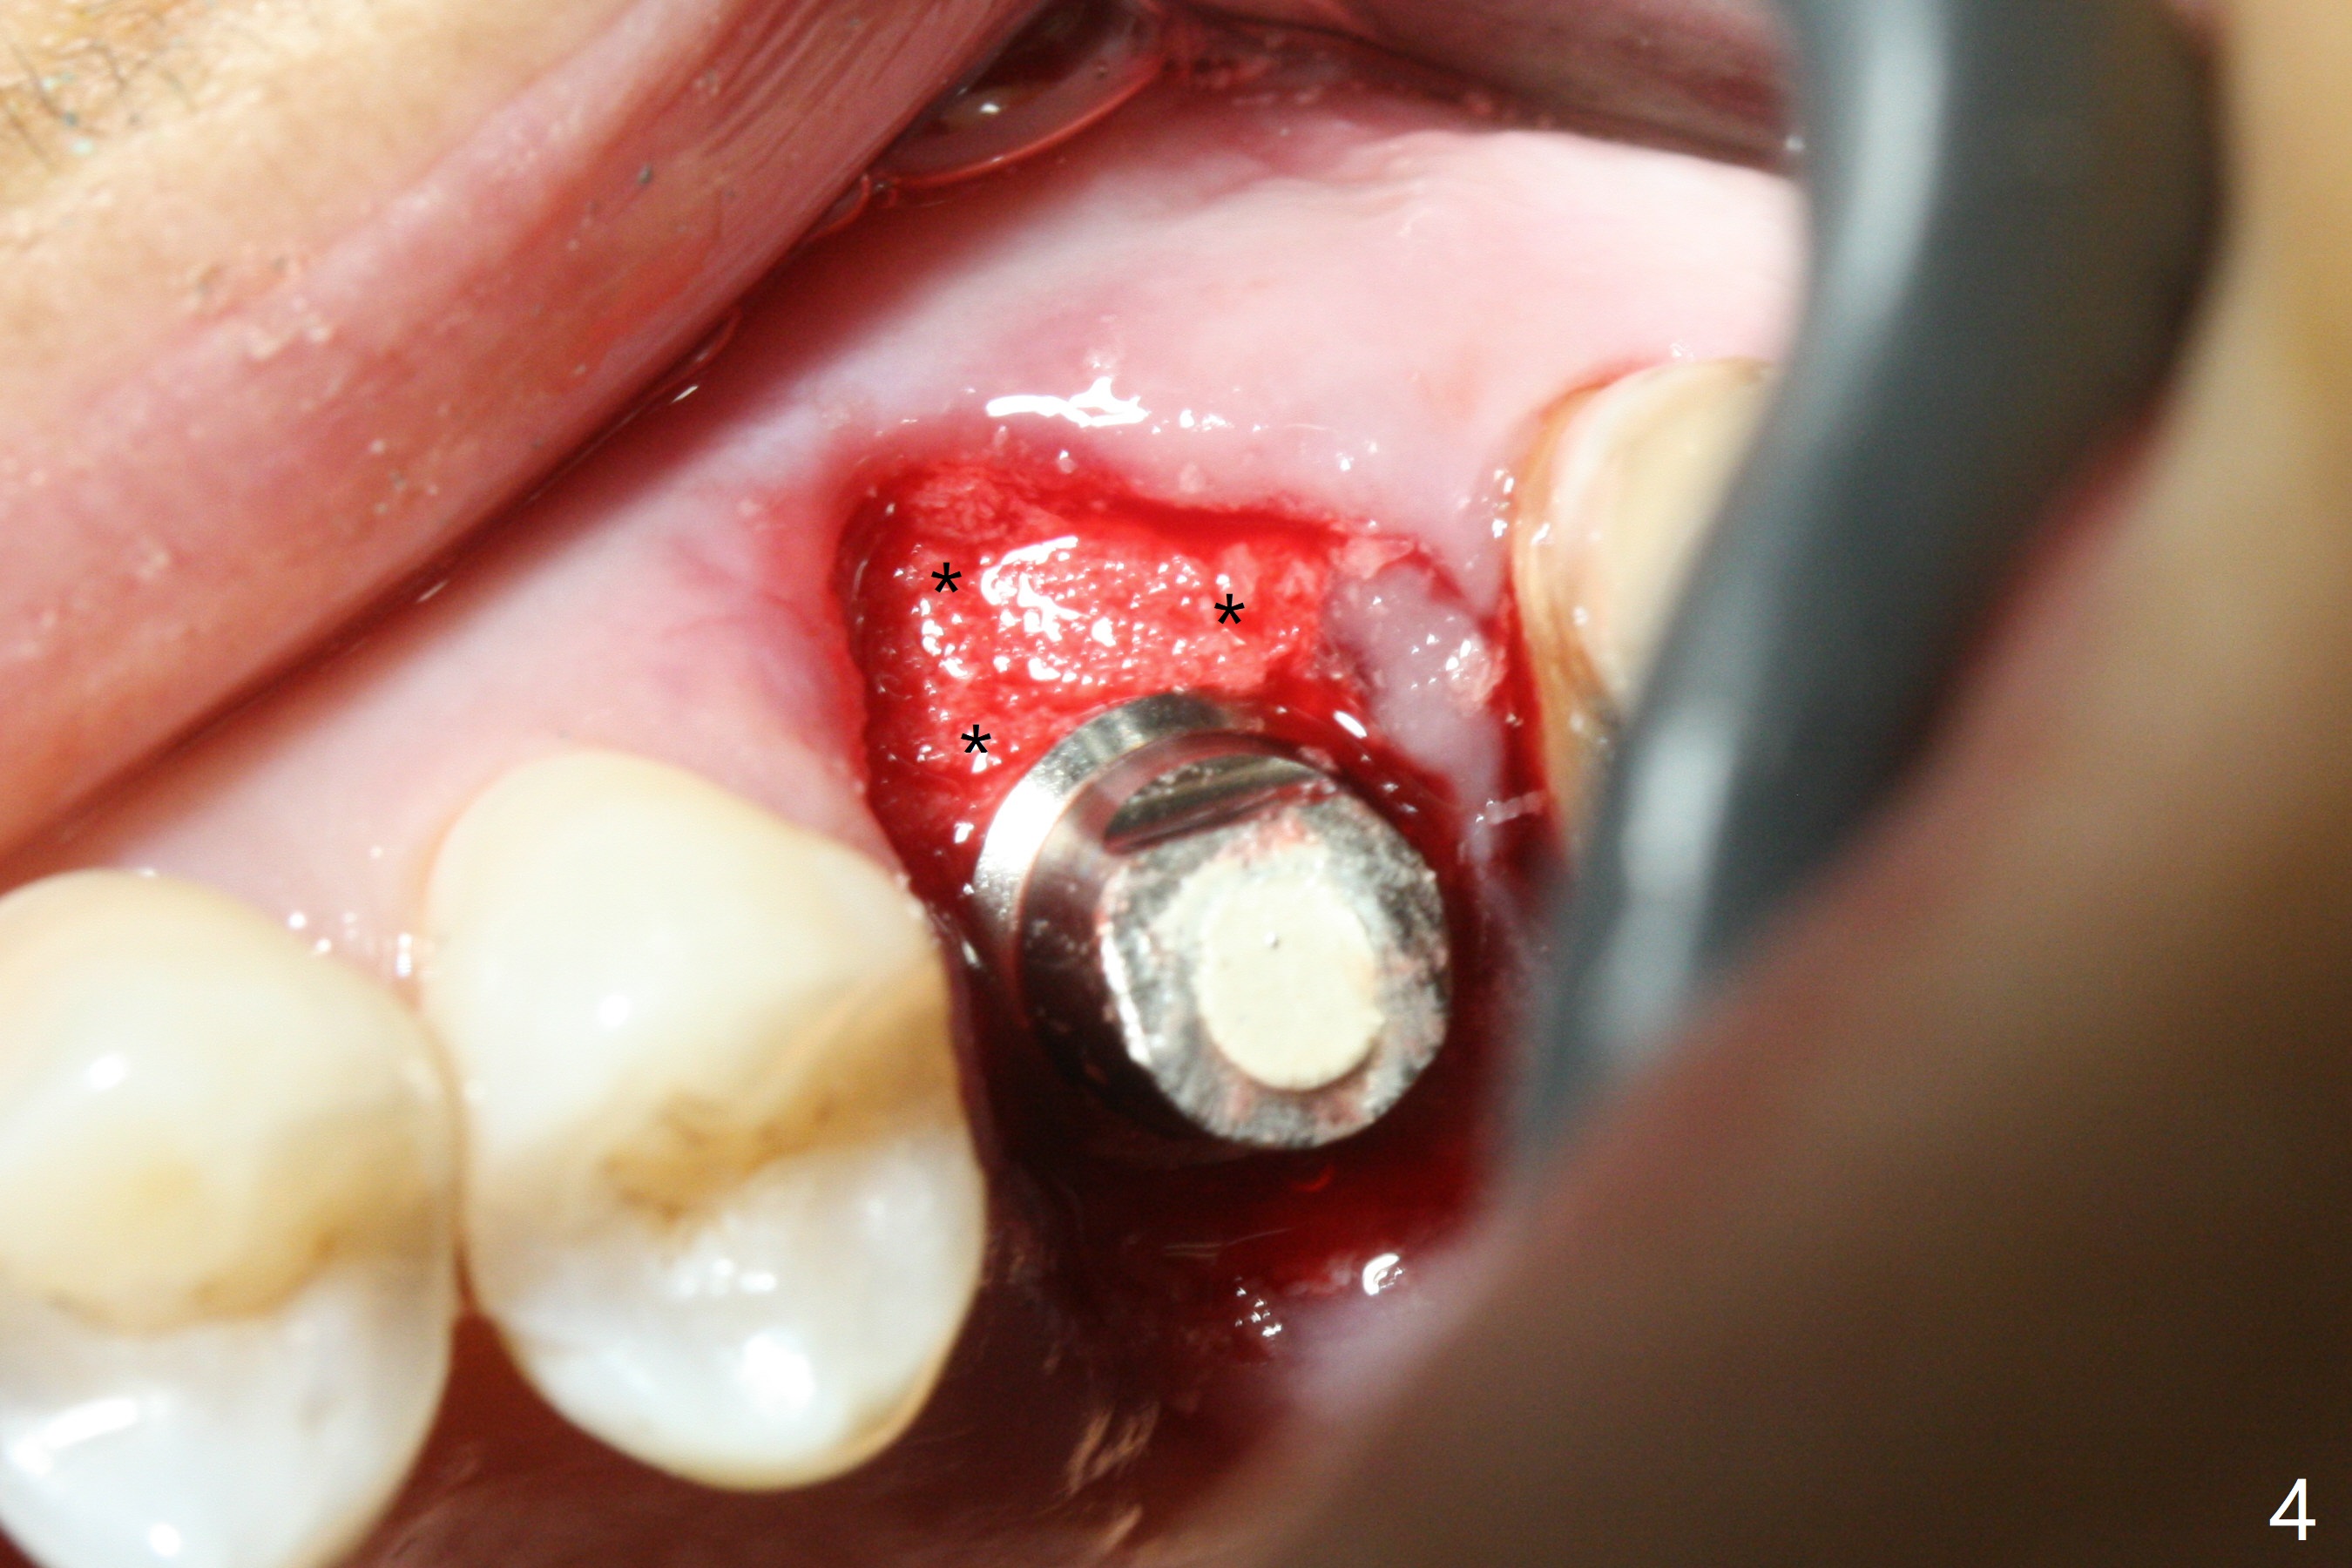

After removal of granulation tissue from the sockets associated with the fractured tooth at #14 (Fig.1 (* granulation tissue)) and initial osteotomy in the septum with a 2 mm drill for 8.5 mm, the sinus floor is penetrated by a parallel pin (Fig.2). But the sinus membrane remains intact until osteotomy finishes with a 4.8 mm drill. Following sinus lift with Vera Graft with autogenous bone (Fig.3 red *), a 5.5x10 mm implant is placed ~ 1 mm coronal to the septal crest and 1-3 mm apical to the surrounding crest (mesiodisto-buccopalatal, >55 Ncm). After further bone graft around the implant (Fig.3 white *), a 6.5x4(3) mm abutment is inserted with the 3rd round of grafting (Fig.3,4 black *). An immediate provisional is fabricated to keep the allograft in place. The implant seems to have osteointegrated 5 months postop (Fig.5).